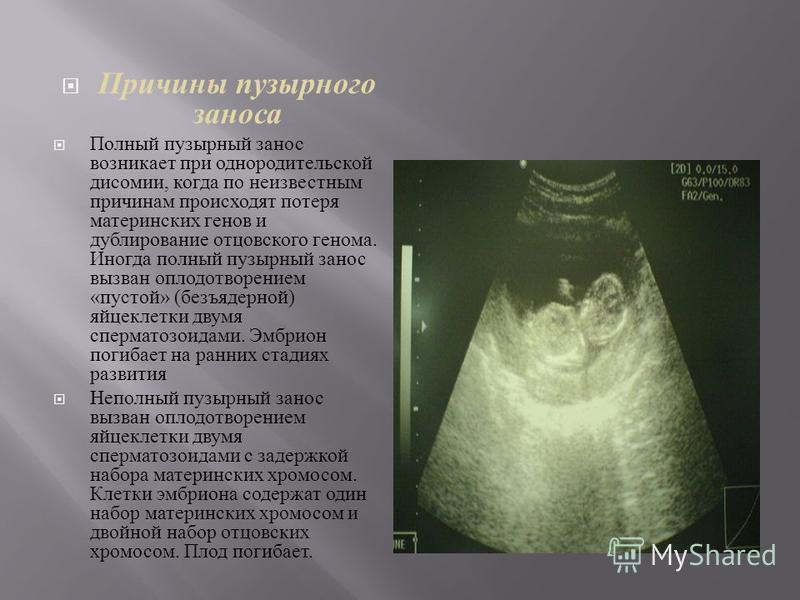

Медицина и диагностика: Инвазивный пузырный занос на УЗИ

Раздел: Альбом идей